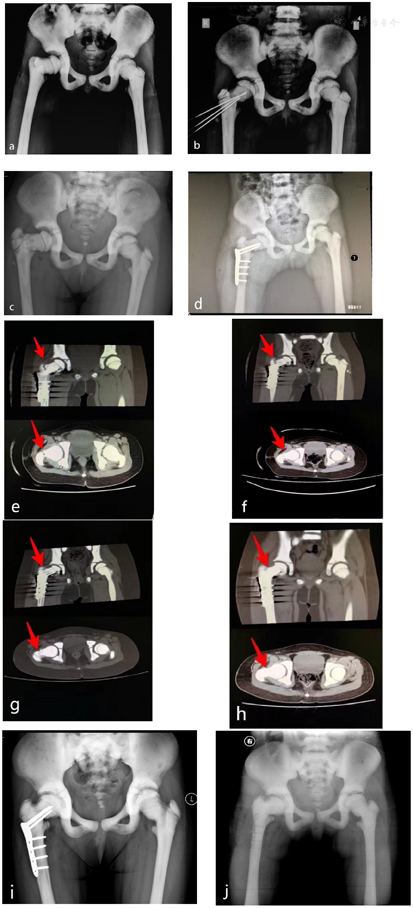

患儿,女,9岁。2017年5月右侧髋部摔伤,患儿主诉疼痛,活动受限。于当地医院就诊,拍摄双髋正位X线(图a)示:弥漫性骨密度增高,骨小梁模糊,骨皮质增厚,髓腔狭窄,符合石骨症X线表现,右侧股骨颈骨质连续性中断,诊断为右侧股骨颈骨折,石骨症。行克氏针内固定手术治疗(图b),术后5个月克氏针取出,复查X线(图c)示骨折未愈合,随后2017年10月于我院手术,行股骨颈骨折闭合复位,钢板内固定术(图d),术后石膏固定6个月,拆除石膏后继续支具固定4个月。

患儿年龄较小,体型瘦弱,皮下脂肪层较薄,对疼痛耐受差,并考虑其为石骨症患者,骨脆性较大,放散式冲击波能量较低,更为安全。因此第一疗程选择使用放散式冲击波治疗3次,第一疗程结束后2个半月复查,CT结果显示患者骨折断端有生长迹象,但进展并不理想。经骨科会诊,考虑钢板位置良好,股骨对位对线较第一疗程无明显差异,可继续保守治疗。根据第一疗程治疗效果考虑石骨症患者骨密度高、骨皮质较厚,低能量的局部血运刺激难以促进骨痂生长。聚焦式冲击波穿透能力较强,可达到皮下较深位置。因此第二疗程我们选择使用能量较高的聚焦式冲击波治疗3次,在安全范围内提高治疗剂量。第二疗程结束后三个月,对病人进行随访,复查CT显示有大量骨痂通过骨折线,较第一疗程进展明显,并在治疗结束一年后拆除钢板,现恢复良好。